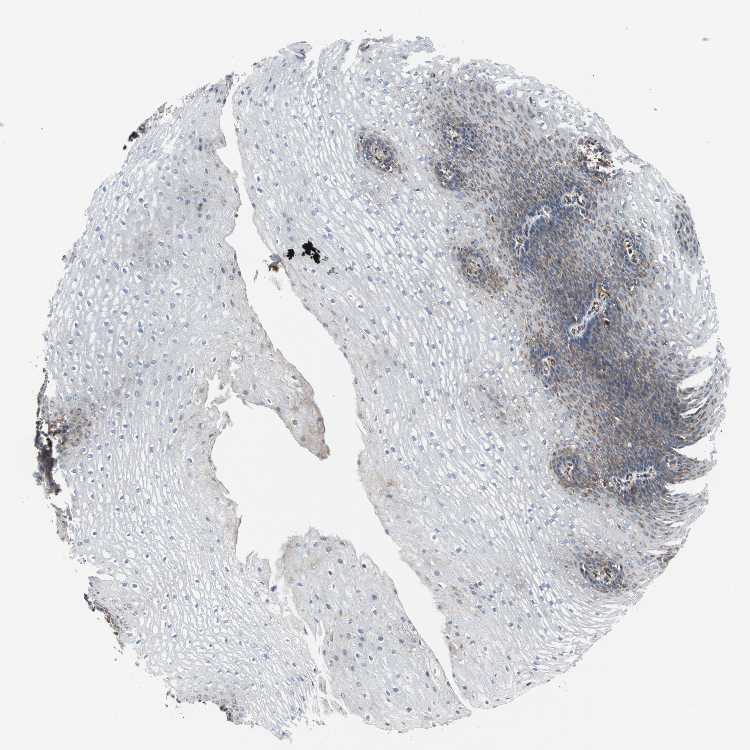

ESOPHAGUS - Antibody stainingi

Antibody staining in the annotated cell types in the current human tissue is reported as not detected, low, medium, or high, based on conventional immunohistochemistry profiling in selected tissues. This score is based on the combination of the staining intensity and fraction of stained cells.

Each image is clickable and will lead to virtual microscopy that enables deeper exploration of all samples and also displays staining intensity scores, fraction scores and subcellular localization as well as patient and tissue information for each sample.

Antibody HPA020099Antibody HPA020100Antibody CAB004280

Squamous epithelial cells Not detectedNot detectedLow